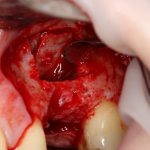

Кстати, обрати внимание на ширину альвеолярного гребня (левая картинка). Она чуть меньше 3 мм. Это объясняет, почему я засомневался в возможности установки имплантатов одновременно с остеопластикой. Понятно и без КЛКТ.

Наперво, мне нужно удалить разрушенный зуб и получить костный аутотрансплантат.

Возвращаемся к основной операционной области. Еще раз посмотрим на альвеолярный гребень, поофигеваем от его ширины и моих грандиозных планов: